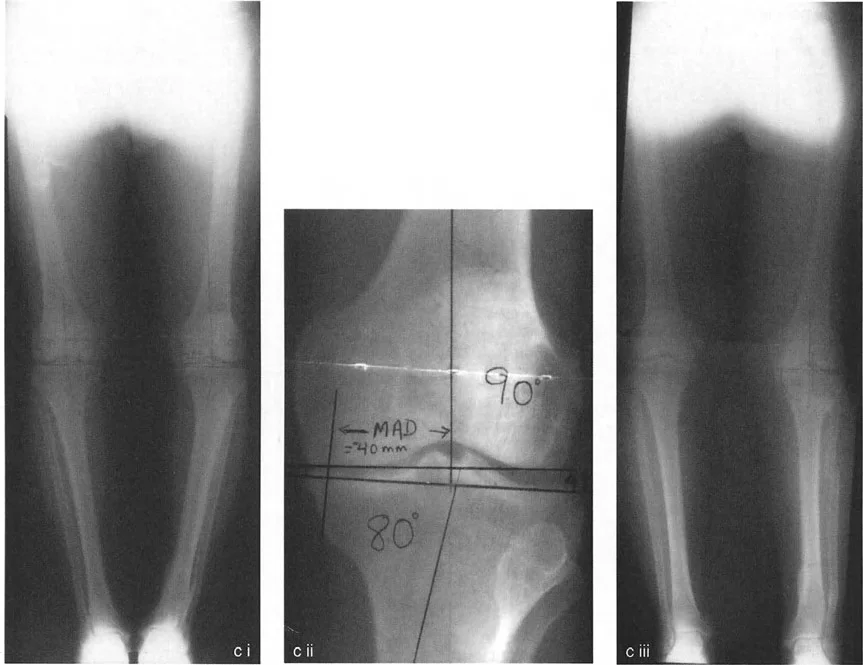

2. التصوير الطبي

- الأشعة السينية (X-rays): تُعد الأشعة السينية هي الأداة التشخيصية الأولية والأكثر أهمية. تُظهر الأشعة السينية تضيق المسافة المفصلية (مؤشر على تآكل الغضروف)، وتغيرات في العظام (مثل النتوءات العظمية)، وتشوهات المحاذاة. تُؤخذ الأشعة السينية عادةً أثناء الوقوف لتقييم توزيع الوزن على المفصل.

- تحليل المحاذاة الميكانيكية الشامل (MAT): يستخدم الدكتور هطيف هذا التحليل المتقدم لتحديد مصدر الخلل في المحاذاة بدقة، سواء كان في عظم الفخذ أو الساق أو كليهما، وأيضًا لتقييم مدى تباعد خط المفصل (JLCA) الناتج عن رخاوة الأربطة أو فقدان الغضروف.